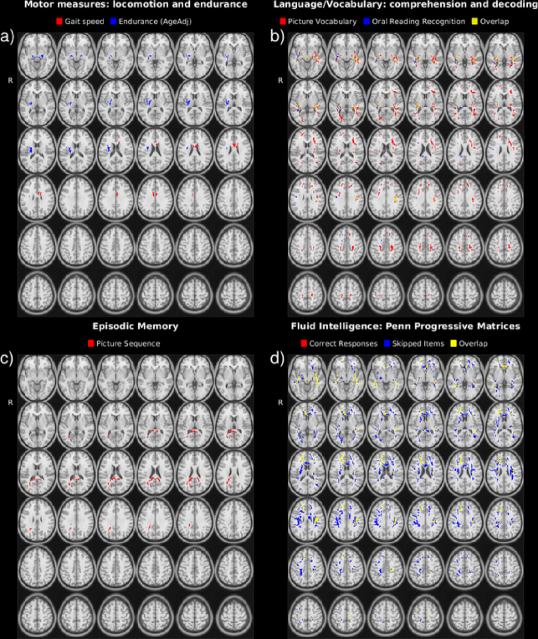

The HCP ODFs also correlate with neurocognitive measures (Fig. 10 and 11). Walking endurance (Fig. 10a and 11a) predictably relates to the corticospinal tract, while the frontal part of the corpus callosum indicated in gait speed has been identified before when comparing endurance athletes with non-athletes (Raichlen et al., 2016) and when studying the effect of treadmill training after stroke (Enzinger et al., 2009). Language recognition and comprehension tasks (Fig. 10b and 11b), as measured by the Oral Reading and Picture Vocabulary test, correlate with ODFs in areas identified by fMRI work (Berl et al., 2010): posterior superior temporal gyrus and inferior frontal gyrus connected by stretches of the arcuate fasciculus pathway/superior longitudinal fasciculus III. Besides these areas, language comprehension also relates with ODFs in the medial frontal gyri and the left precuneus (Schmithorst et al., 2007). Our analysis further connects the Episodic Memory measure with the posterior cingulate and precuneus, though not with the medial temporal cortex (Fig. 10c and 11c). These areas have been shown to deactivate in episodic memory tasks (Dickerson and Eichenbaum, 2010). Lastly, Fluid Intelligence correlates widely with ODFs in the prefrontal, parietal and temporal cortex as indicated before (Gray et al., 2003) as well as with ODFs along tracts connecting these regions (Fig. 10d and 11d).